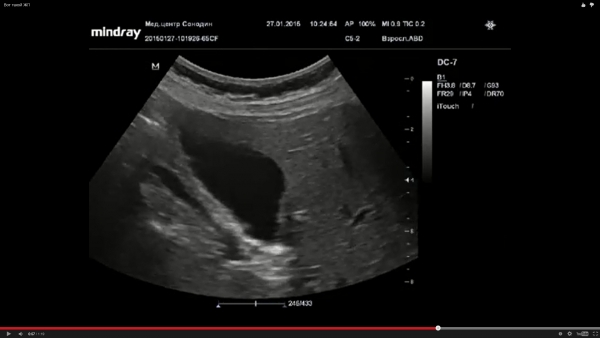

По поводу ролика Дмитрия - я бы написал здесь как раз этот пресловутый хронический холецистит, стенки фиброзно изменены.. Ну и перегиб, понятно.

Пациент как раз пришел с предыдущим УЗ- заключением , а я "снял" очередной хр.холецистит.

и как насчет того, что по всем канонам, толщина стенки измеряется на стороне прилежащей к печени?

Серега1971, могу и по передней стенке измерить, результат будет тот же!

Давай , я даже из ставки вижу, что она меньше 2 мм

Ну да, где то так 2-3 мм.!

Я редко когда измеряю стенку ЖП, уже на глаз видно, что она нормальная.

Только при явной патологии.

А здесь норма!

Не понимаю. На каком основании тут можно писать, что стенка фиброзно-изменена?

Всегда было споры на счет существования диагноза "хр. некалькулезный холецистит",а тут прямо на УЗИ так часто.. ...